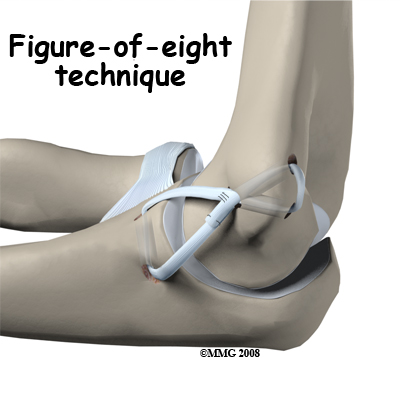

Another common technique to reconstruct the ulnar collateral ligament is the technique. In this technique, the tendon graft is threaded through two pairs of holes - two drilled in the medial epicondye and two in the ulna. The graft is looped through the holes in a figure of eight fashion. The two ends of the tendon are sutured to the tendon itself.